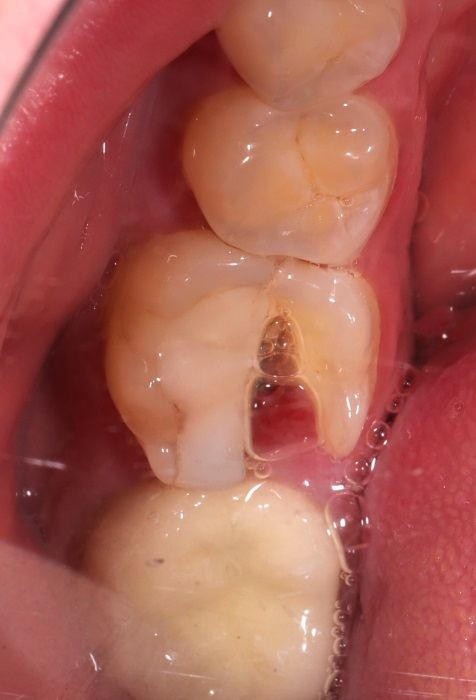

Зуб 46 разрушен очень сильно, и больше не может выполнять функции.

На фото вид операционной зоны после операции и через 3 месяца дней после.

Как и всегда, я стараюсь провести максимальный комплекс в одну операцию: удаление, имплантация, костная пластика, пластика слизистой, установка заживляющего абатмента.

Протезировать, а тем более реставрировать его бесполезно и бессмысленно. Принято решение заменить его имплантом Strauman SLActive (система входит в топ 5 по миру).

46 — трещина в медиальном корне — причина титанов штифт установленный под неправильным углом. Как следствие трещины переодические ноющие боли после приема пищи.

Две недели после операции.

Что сделали: атравматичное удаление, установка импланта Straumann BLT 4.1x10mm, формирователь, костная пластика, пластика слизистой, APRF. Операцию провели одномоментно — сохранили объём кости, слизистой.